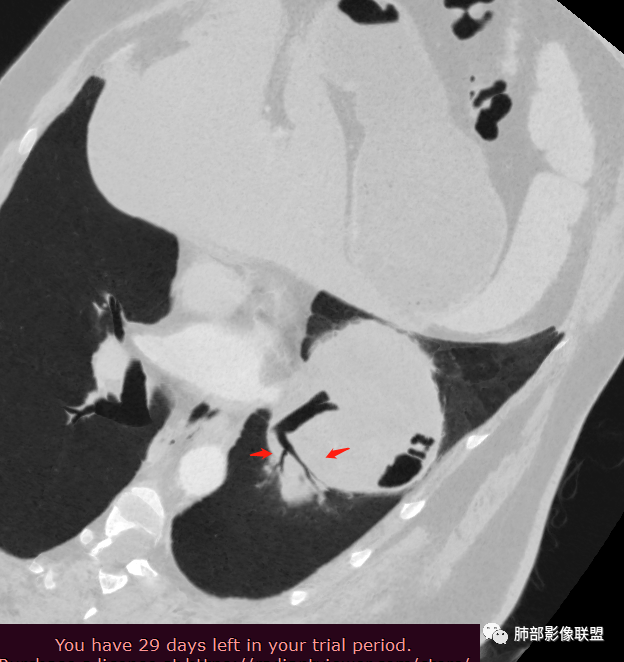

骑跨在斜裂上

局部斜裂稍增厚

下叶基底干支气管受压下移

下叶背段支气管受压稍后内移位,通畅

就是支气管目前基本没有堵塞,只是受压

空气新月征:

新月征很有特点,血管有特点